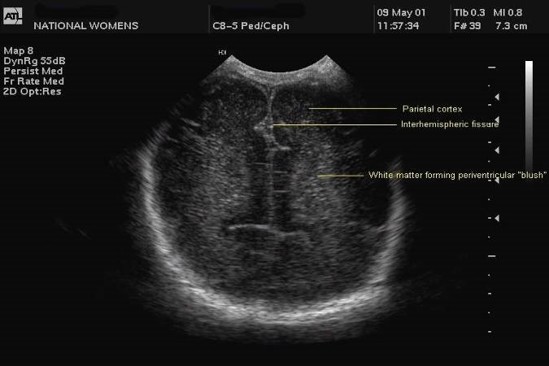

Measurement of the ventricular system needs to be performed on a symmetrical, easily reproducible view. The ventriculo-cranial ratio (VCR) is the ratio of distance between the lateral sides of the ventricles and the biparietal diameter. This is usually expressed as a percentage with a normal value of around 33-36% in a preterm infant. This value is of most use in monitoring the degree of change between successive measurements. An increasing VCR should trigger frequent reassessments with measurements of the cerebral resistive index (see below).